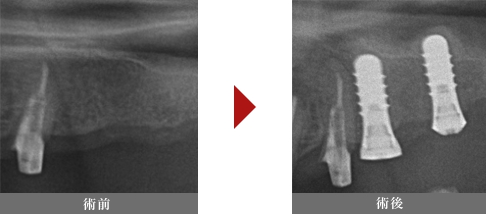

ソケットリフト法 ソケットリフトとは

上顎洞という副鼻腔のうちの一つ、

お鼻と繋がってる空洞の部分の粘膜をインプラント形成窩から1~2mm程持ち上げて骨を足す処置です。

経験の浅い術者でも比較的導入しやすい治療法ですが、盲目下での処置になりますので、

粘膜を破ってしまうような偶発症も想定した場合、上記に記載するサイナスリフトを行える歯科医師が行うべきであると。専門家が警告をしております。

上顎洞の底を持ち上げ、骨補填材を埋め込んだ箇所の インプラントは4ヶ月程で使えるようになります。

症例

20代女性

治療回数:1回

治療費:インプラント埋入費用(通常の治療費)+人工骨材料代(20,000円〜)

リスク:目の下の横付近の腫れの可能性、感染